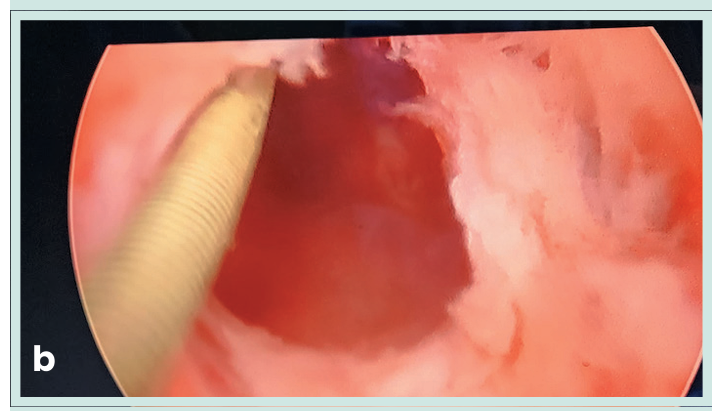

Se realizó una uretrotomía interna con cuchilla fría (Sachse) seguida de dilatación con balón liberador de paclitaxel (10 mm × 60 mm), insuflado a 10 atm durante cinco minutos luego a 12 atm por dos minutos. Se colocó una sonda Foley de silicón 16 Fr durante 48 horas.